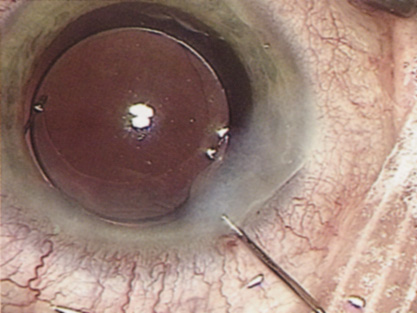

INTRAOCULAR LENS IMPLANTATION

At the turn of the century, the incidence of posterior capsular opacification (PCO), the most common untoward event after surgery, was plummeting as the result of a square edge design on the IOL optic. The haptics themselves had evolved from Prolene material to polymethylmethacrylate and then Alcon introduced a soft haptic on a single-piece acrylic platform. Every company developed an injector for improved IOL insertion, and industry was teaming up with innovative surgeons in developing a number of optic modifications. Attempts to achieve multifocality with diffractive optics had been introduced by 3M and their design team of Richard Lindstrom, John Sheets, and Robert Osher. This technology was placed on the back burner until Allergan developed the array multifocal IOL. Alcon purchased and improved the 3M defractive optic and introduced ReStor IOL on a single-piece acrylic platform. The surgical assault on presbyopia accelerated as Eyeonics developed the Crystalens, the first IOL with a pliable optic aimed at generating accommodation, a concept introduced a decade before by Spencer Thornton.33 A toric optic was developed by Staar Surgical; Pharmacia introduced Tecnis, the first spherical aberration-correcting IOL; and Alcon developed the first blue-light–filtering optic to provide macular protection. The once narrowly defined specialty of cataract and IOL surgery was exploding with new ideas and technologies. Smaller-incision IOLs were being designed that could be injected through <2-mm incisions. A host of surgeons, including Amar Agarwal, Jorge Alio, Richard Packard, Hiroshi Tsuneoka, Virgilio Centurion, Howard Fine, and Randy Olson, were exploring microincisional cataract surgery through 1.5-mm incisions by separating the sleeveless ultrasound tip from the irrigating chopper.